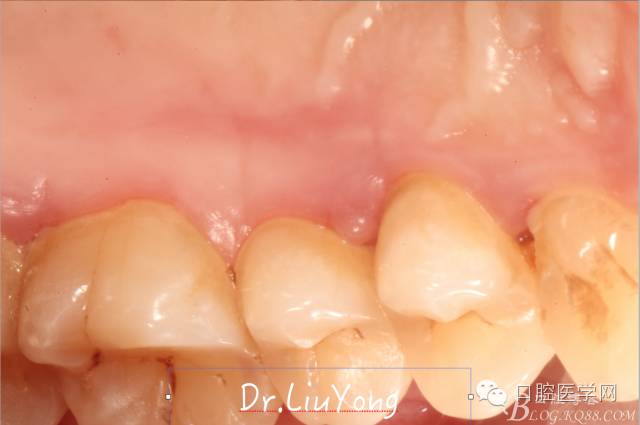

術(shù)后兩周,復(fù)查,A1達到了完全的根面覆蓋,B1牙齦退縮由原來的3.5mm減少到1mm,B2近中牙齦也得到部分的恢復(fù),同時所有牙齦邊緣都通過手術(shù)增厚。如上圖

A區(qū)結(jié)締組織取瓣區(qū)域的愈合后照片,如上圖